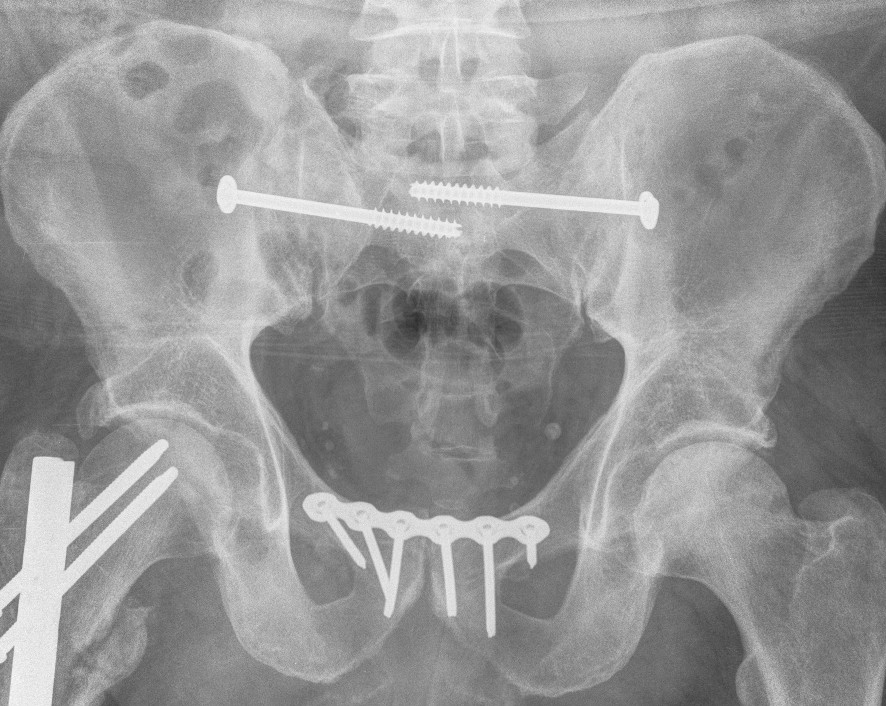

Post-operative XRs: AP, outlet and inlet views

Sacro-iliac screws

Insert 6.5 mm partially threaded cannulated screw, to aid compression

Post operative

Check screw position with CT